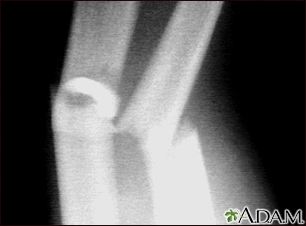

Fracture, forearm - x-rayBackFracture, forearm - x-rayThis x-ray shows broken (fractured) forearm bones (radius and ulna). E-mail FormEmail ResultsName:Email address:Recipients Name:Recipients address:Message: